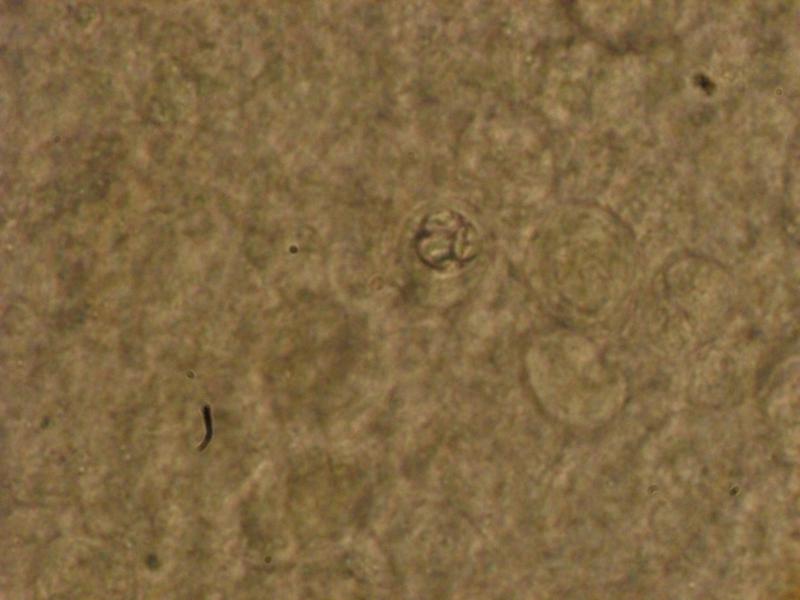

Следующим нашим объектом будет КОКЦИДИЯ вызывающая КОКЦИДИОЗНЫЙ ЭНТЕРИТ . многие любители золотых рыбок видели её работу (в основном азиатских да и местных то-же) , рыбка "усыхает" , остается только голова и брюхо "выпуклое во внутрь" с тонкой спиной .Живет в кишечнике больной рыбы и через экскременты (светлые- белесые, длинные нити, здесь их то-же легко увидеть в микроскоп) заражает всех остальных.Болеют все формы золотых и карпы .Может сохранять жизнеспособность до 7 лет в ГРУНТЕ, КОРНЯХ РАСТЕНИЙ (И СВОИХ И КУПЛЕННЫХ) , В ЩЕЛЯХ ДЕКОРАЦИЙ И ЭЛЕМЕНТАХ ФИЛЬТРОВ, В ЩЕЛЯХ СИЛИКОНА .При покупке больную рыбу всегда видно, перед поселением в аквариум необходим АКТИВНЫЙ КАРАНТИН , карантинный аквариум потом моется с БЕЛИЗНОЙ. На фото всегда хорошо видны округлые шарики как-бы с дольками внутри . http://pisciculture.ru/action/disease?id=194 Лечится легко, выводится из аквариума -- долго. Чеснок - раз в неделю дает положительный результат . http://www.aquaforum.ua/attachment.p...1&d=1364644072 http://www.aquaforum.ua/attachment.p...1&d=1364644205 http://www.aquaforum.ua/attachment.p...1&d=1364644298